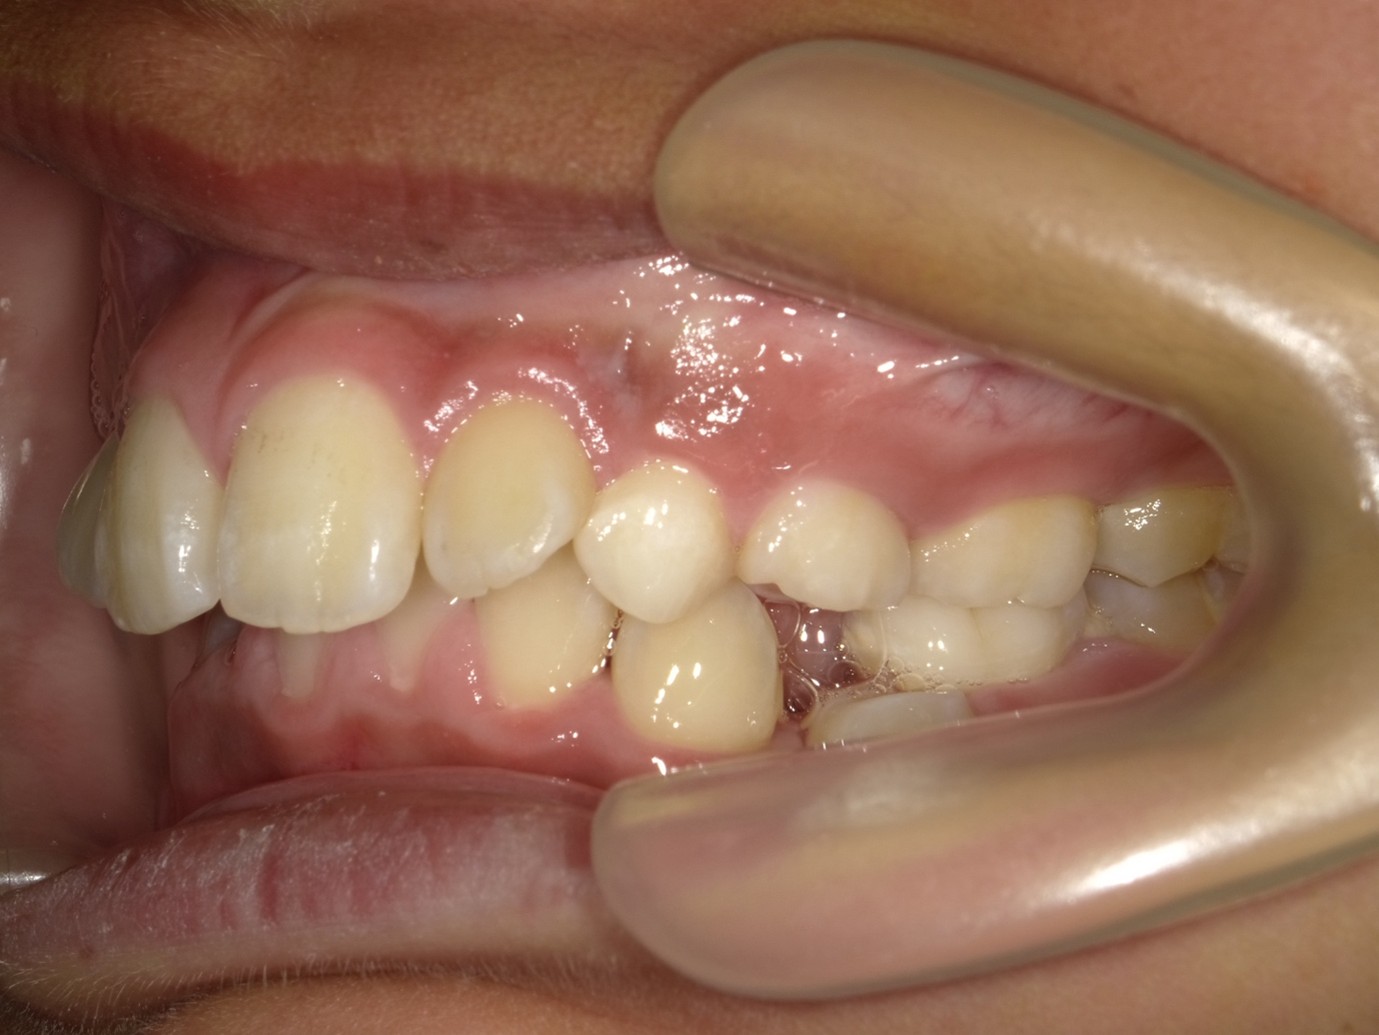

| 症例分類 | 過蓋咬合 |

|---|---|

| 主訴 | 他の歯科医院で咬み合わせを指摘された |

| 年齢 | 10歳10ヶ月 |

| 性別 | 男性 |

| 抜歯部位 | なし |

| 使用装置 | 拡大装置、咬合斜面板(取り外し式の矯正装置) |

| 治療期間 | 3年4ヶ月 |

| 保定装置 | 咬合斜面板 |

| 費用 | 相談料0円、検査料55,000円 動的矯正治療費330,000円 調整料6,600円×30回分 保定装置料0円 |

| リスク・注意点 | 上の顎の大きさに対して下の顎が小さく、過蓋咬合が生じています。これらを改善するために、幅の狭搾している歯列を側方に拡大したのち、下顎の成長を促進しました。

歯の動き方には個人差があり、予想された治療期間が延長する可能性があります。 治療中は矯正歯科装置が歯の表面に付いており、歯が磨きにくくなるため、むし歯や歯周病が生じるリスクが高まります。ハミガキを適切に行ってお口の中を常に清潔に保ち、さらに、かかりつけ歯科医に定期的に受診することが大切です。 矯正歯科装置の使用状況、定期的な通院など、矯正歯科治療には患者さんの協力が必要であり、それらが治療結果や治療期間に影響します。 治療の経過によっては当初予定していた治療計画を変更する可能性があります。保定装置の装着時間が十分確保できない場合、歯並びや、咬み合せの「後戻り」が生じる可能性があります。 上下両側第二大臼歯の萌出を観察する必要があります。(治療後の写真は成人矯正開始直前の資料です。) |